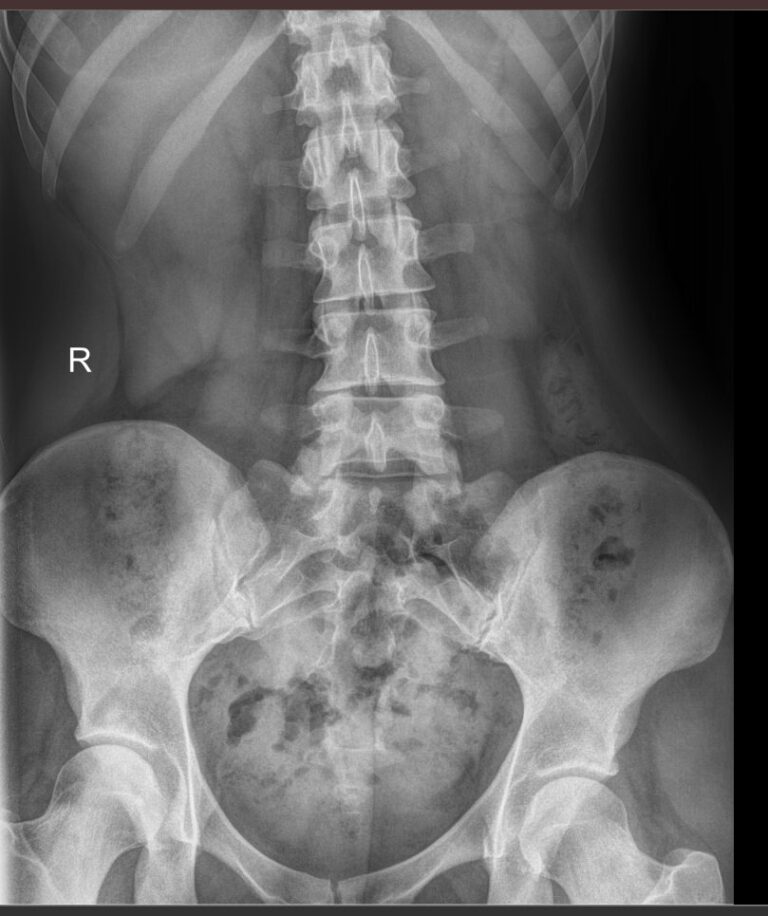

Что показывает обзорный рентген мочевыделительной системы

У здорового человека обзорный снимок покажет:

- Тени почек и мочевого пузыря;

- Мочеточники ― только при значительных изменениях;

- Нижние грудные, поясничные позвонки, ребра, тазовые кости;

- Тени поясничных мышц.

На рентгенограмме будут видны такие патологии, если они есть:

- Увеличение или уменьшение почек в размерах ― признак врожденной аномалии, воспаления и других заболеваний;

- Камни в почках и мочевом пузыре;

- Коралловидные камни в почках;

- Конкременты в желчном пузыре;

- Флеболиты ― камни вен малого таза;

- Опухоли и очаги склероза в костях малого таза;

- Обызвествленные хрящи ребер и лимфоузлы;

- Инородные тела.